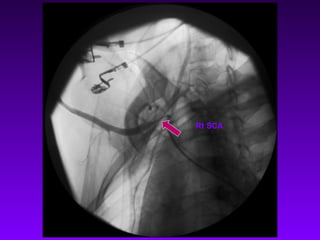

Lt SCA

Rt SCA

CC A

Abd Aorta

Rt CCA Long

Stenosis

Lt SCA Not Seen

Rt SCA Narrowing